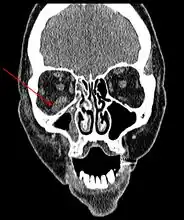

Imaging is often performed, such as CT scan of lungs and sinuses.[38] Signs on chest CT scans, such as nodules, cavities, halo signs, pleural effusion and wedge-shaped shadows, showing invasion of blood vessels may suggest a fungal infection, but does not confirm mucormycosis.[16] A reverse halo sign in a person with a blood cancer and low neutrophil count, is highly suggestive of mucormycosis.[16] CT scan images of mucormycosis can be useful to distinguish mucormycosis of the orbit and cellulitis of the orbit, but imaging may look identical to those of aspergillosis.[16] MRI may also be useful.[39]

CT head (axial): invasion of right maxillary sinus (presented with double vision, swollen painful eye). -

CT head (coronal) of same person. -